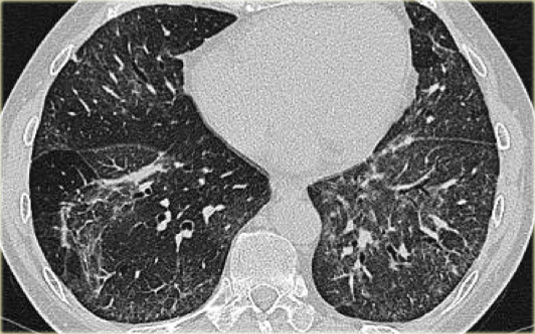

Sarcoidosis: hình ảnh điển hình với các nốt dọc theo bó mạch phế quản và các khe liên thùy. Lưu ý hạch vôi hóa một phần ở rốn phổi trái.

Dấu hiệu HRCT trong Sarcoidosis

- Dấu hiệu thường gặp:

- Các nốt nhỏ phân bố theo đường bạch huyết (dọc theo bề mặt dưới màng phổi và các khe liên thùy, dọc theo vách liên tiểu thùy và bó mạch phế quản).

- Ưu thế ở vùng trên và giữa phổi.

- Hạch to ở rốn phổi trái, rốn phổi phải và cạnh khí quản (dấu hiệu 1-2-3). Thường kèm vôi hóa.

Hình ảnh điển hình của sarcoidosis với hạch to rốn phổi và các nốt nhỏ dọc theo bó mạch phế quản (mũi tên vàng) và dọc theo các khe liên thùy (mũi tên đỏ).

Hình ảnh chi tiết với biểu hiện HRCT điển hình gồm các nốt dọc theo bó mạch phế quản (mũi tên đỏ) và các khe liên thùy (mũi tên vàng).

Đây là phân bố theo đường bạch huyết điển hình của các nốt.

Bên trái là một hình ảnh điển hình khác của sarcoidosis với hạch to trung thất và các nốt nhỏ phân bố theo đường bạch huyết dọc theo bó mạch phế quản và dọc theo các khe liên thùy (mũi tên vàng).

Luôn tìm kiếm các nốt nhỏ dọc theo các khe liên thùy, vì đây là dấu hiệu rất đặc hiệu và điển hình của sarcoidosis.